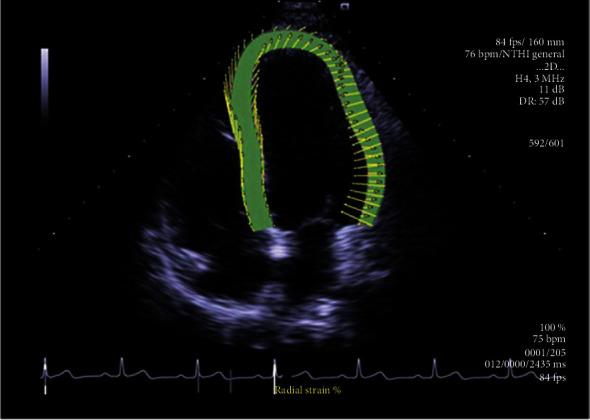

This was a prospective cohort study of 72 patients diagnosed with CA and admitted to the PLA General Hospital between November 2017 and April 2021. Demographic, clinical, laboratory, electrocardiographic, conventional ultrasound, endocardial LS during LV systole (LV ENDO LSsys), and myocardial strain data were recorded. Survival was assessed. All-cause mortality was the endpoint. Follow-up was censored on September 30, 2021.

The mean follow-up was 17.1 ± 12.9 months. Among the 72 patients, 39 died, 23 survived, and 10 were lost to follow-up. Mean survival for all patients was 24.7 ± 2.2 months. Mean survival was 32.7 ± 2.4 months among patients with NYHA class II, 26.6 ± 3.4 months for NYHA class III, and 5.8 ± 1.1 months for NYHA class IV. The multivariate Cox proportional hazard regression model showed that NYHA class (HR = 3.42, 95% CI: 1.36-8.65, = 0.002), log-proBNP level (HR = 1.40, 95% CI: 1.17-5.83, = 0.03), and ENDO LSsys of the LV basal level (HR = 1.25, 95% CI: 1.05-1.95, = 0.004) were independent prognostic factors for CA.

NYHA class, proBNP level, and ENDO LSsys of the LV basal level were independently associated with the survival of patients with CA.